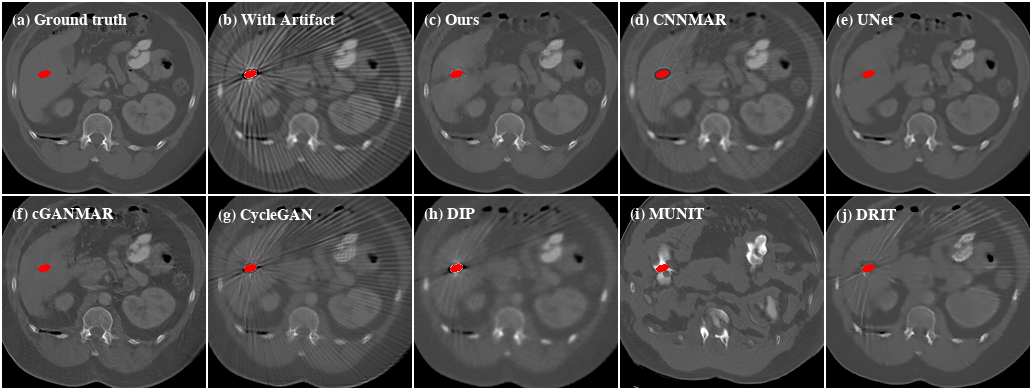

Refer to caption

Figure 10: Qualitative evaluation results of CL2.

Performance on clinical data.    Next, we investigate the performance of the proposed method on clinical data. Since there are no ground truths available for the clinical images, only qualitative comparisons are performed. The qualitative evaluation results of CL1 are shown in Figure 9. Here, all the supervised methods are trained with paired images that are synthesized from the artifact-free group of CL1. We can see that UNet and cGANMAR generalize poorly when applied to clinical images (Figure 9(d) and 9(e)). CNNMAR is more robust as it corrects the artifacts in the sinogram domain. However, such a sinogram domain correction also introduces secondary artifacts (Figure 9(c)). For the more challenging cross-modality artifact reduction task with CL2 (Figure 10), all the supervised methods fail. This is not totally unexpected as the supervised methods are trained using only CT images because of the lack of artifact-free CBCT images. Similar to the cases with SYN, the other unsupervised methods also show inferior performances when evaluated on both the CL1 and CL2 datasets. By contrast, our method consistently delivers high-quality artifact reduced results on clinical images.